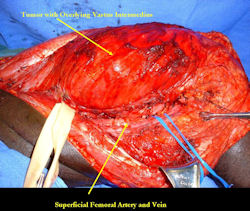

Limb-sparing surgery for osteosarcoma of distal femur – Intraoperative photos